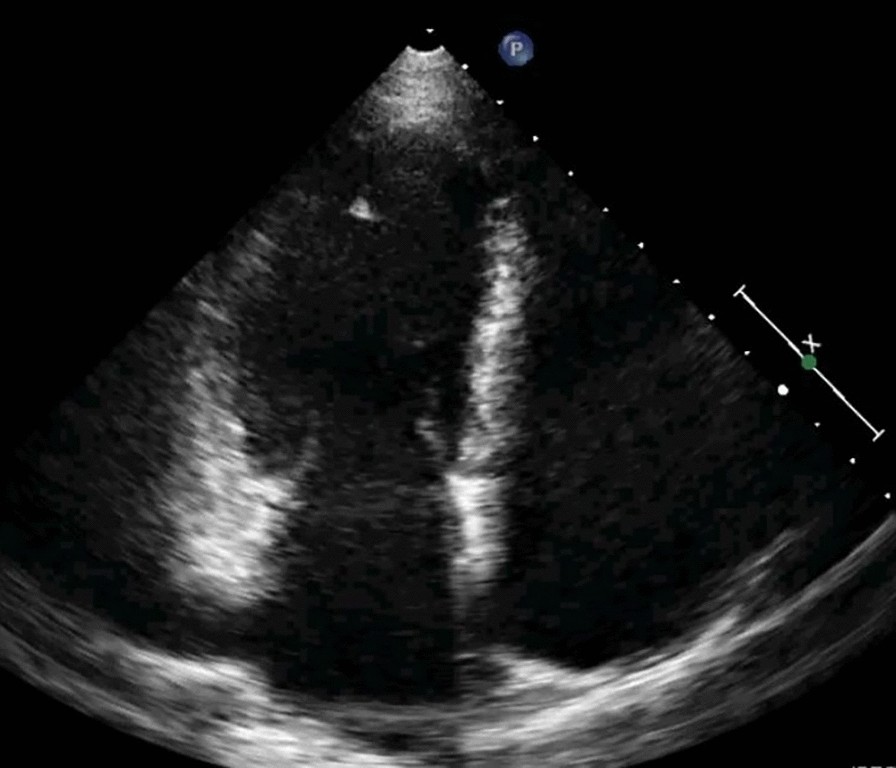

Fig. 5From: Left atrial ıntramural hematoma after radiofrequency catheter ablation of left lateral accessory pathwayControl transthoracic echocardiogram in apical four-chamber view shows complete resolution of intramural hematomaBack to article page